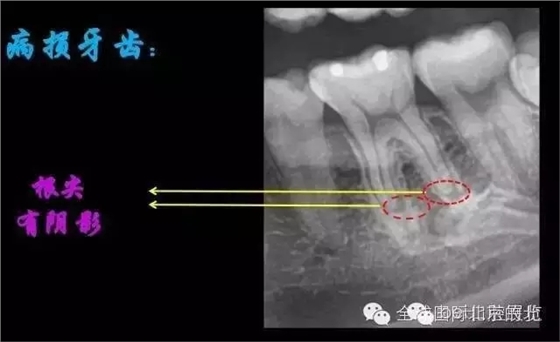

我們?cè)賮砜纯椿佳溃?p>

X-RAY示:近遠(yuǎn)中牙根都有陰影存在,牙周膜都有些許增寬,近中頸部位置牙體有低密度減低影,就是楔狀缺損的位置。 病因分析:楔狀缺損的深齲致牙髓壞死引起的根尖炎癥,應(yīng)囑患者以后改變刷牙方式 診斷:36慢性根尖炎急性發(fā)作 治療方案:36做根管治療,然后充填完成后行冠修復(fù)。 首次治療過程:開髓引流,無明顯滲出液,pathfile疏通根管,沖洗,氫氧化鈣暫封,一周復(fù)查。